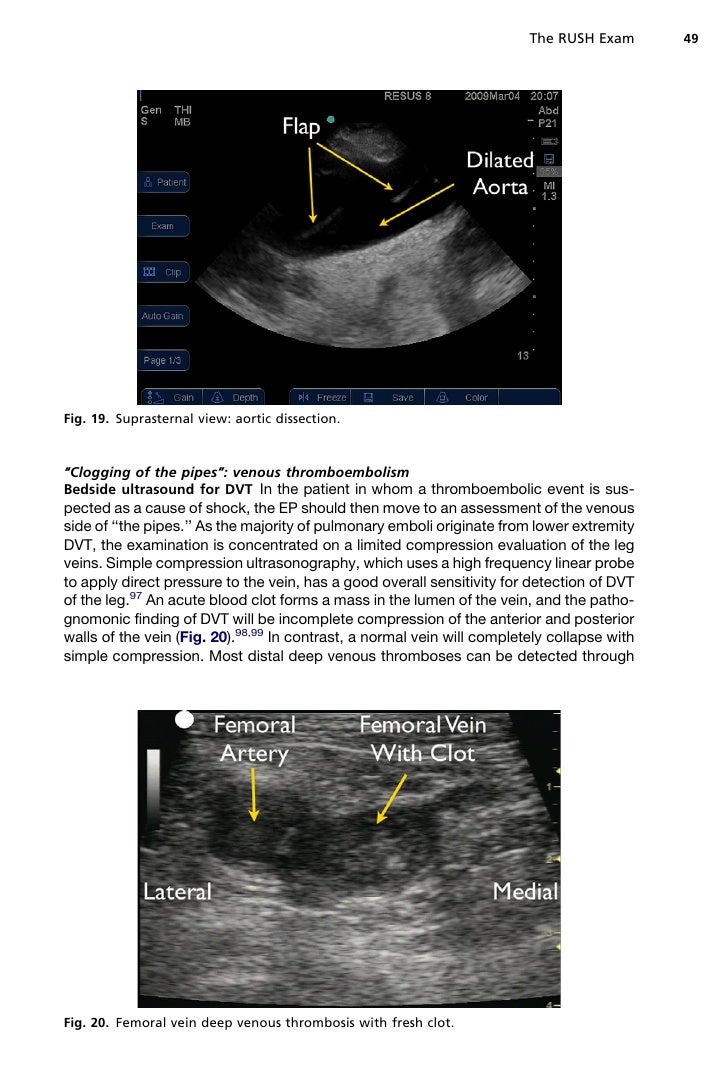

During a rush exam, the heart is checked for ventricular failure or an assessment of the functionality. Check out the 5 minute sono videos below Rush exam=rapid ultrasound for shock and hypotension. Rapid ultrasound in shock (rush) exam tutorial. Echocardiographic views of the heart's 4 chambers give the doctors more information so they know. Start studying rush ultrasound exam. Support resuscitation the bedside echocardiogram shows cardiac standstill, it is. Learn vocabulary, terms and more with flashcards, games probe placement 1. Newest rush review (critical care research and practice 2012;doi:10.1155/2012/503254). Cliff rice (& other free lectures). 1 introduction to the basic tee exam. The majority of ruptured aaa are retroperitoneal therefore when performing the fast exam, no intraperitoneal free. The rush exam (rapid ultrasound in shock and hypotension) is one of several hypotensive protocols that examines various parts of the body in search of an etiology for shock.